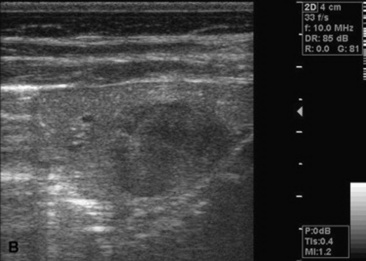

Ultrasonography

Thoracic ultrasonography, a companion to thoracic radiography, is useful for diagnostic, therapeutic, and prognostic evaluation of the extraparenchymal thorax, the pleural space, and the peripheral (superficial) parenchyma of the lung. Unlike thoracic radiography, in which specialized equipment is needed to image the adult large animal, thoracic ultrasonography is an imaging technique readily available to most practitioners. In many instances it is superior to thoracic radiography as an imaging method; examples include evaluation of pleural effusions, assessment of thoracic trauma, evaluation of neoplasms or granulomata, detection of mediastinal masses or abscesses, and guidance of transthoracic lung biopsy.9,10 Ultrasonography is considered greatly superior to thoracic radiography in the detection of rib fractures.11 This imaging technique should be considered for complete evaluation of any large animal with suspected or diagnosed pulmonary disease.

Ultrasonography is generally performed with the patient standing, although in neonates lateral recumbency may be preferred or even necessary, and sound waves are generated by piezoelectric crystals and transmitted to the area of interest through a skin coupling gel, with subsequently reflected echoes detected by the same crystal. Echo signals from all tissue interfaces are displayed on a screen; the image can be photographed for a permanent record or stored digitally. Air trapped beneath the haired skin can interfere with the process, as can excessive skin dirt, so preparation of the acoustic window usually involves hair removal and cleansing in order to get the best image possible.

Although ultrasound waves will not penetrate the aerated portion of the lung, limiting the examination to extraparenchymal surfaces in normal horses, ultrasonography is superior to thoracic radiography in evaluation of these areas of the chest. Small amounts of pleural fluid that would be missed on auscultation, percussion, or thoracic radiographs can be detected, and the amount and character of pleural effusion in each hemithorax can be separately evaluated.9 Clear fluid is anechoic, but inflammatory cells, gas, and fibrin are echogenic, causing opacities that can be seen floating in pleural fluid and altering the general echogenicity of the fluid. Because of this, ultrasound is the method of choice for diagnosis and monitoring of pleural space disease. Ultrasonography should be used to guide catheter placement for drainage of accumulated fluid in the pleural space. The pleural surfaces are imaged well by ultrasound, with thickened or roughened areas easily detected. Lack of normal independent movement of the visceral and parietal pleural surfaces during the respiratory cycle, suggestive of adhesion formation, can be readily monitored.9,10

Consolidated lung is a better acoustic medium than aerated parenchyma and can be well visualized. If there is pleuropneumonia with consolidation or atelectasis caused by compression of the ventral lung by pleural effusion, it will be evident. Pulmonary abscesses or masses extending to the lung surface can be imaged, and ultrasound can be used for guidance for transthoracic biopsy.9,10 Thoracic radiography remains superior to ultrasound in diagnosis of pulmonary parenchymal disease and pneumothorax, but combined the two techniques will improve patient management diagnostically and therapeutically.